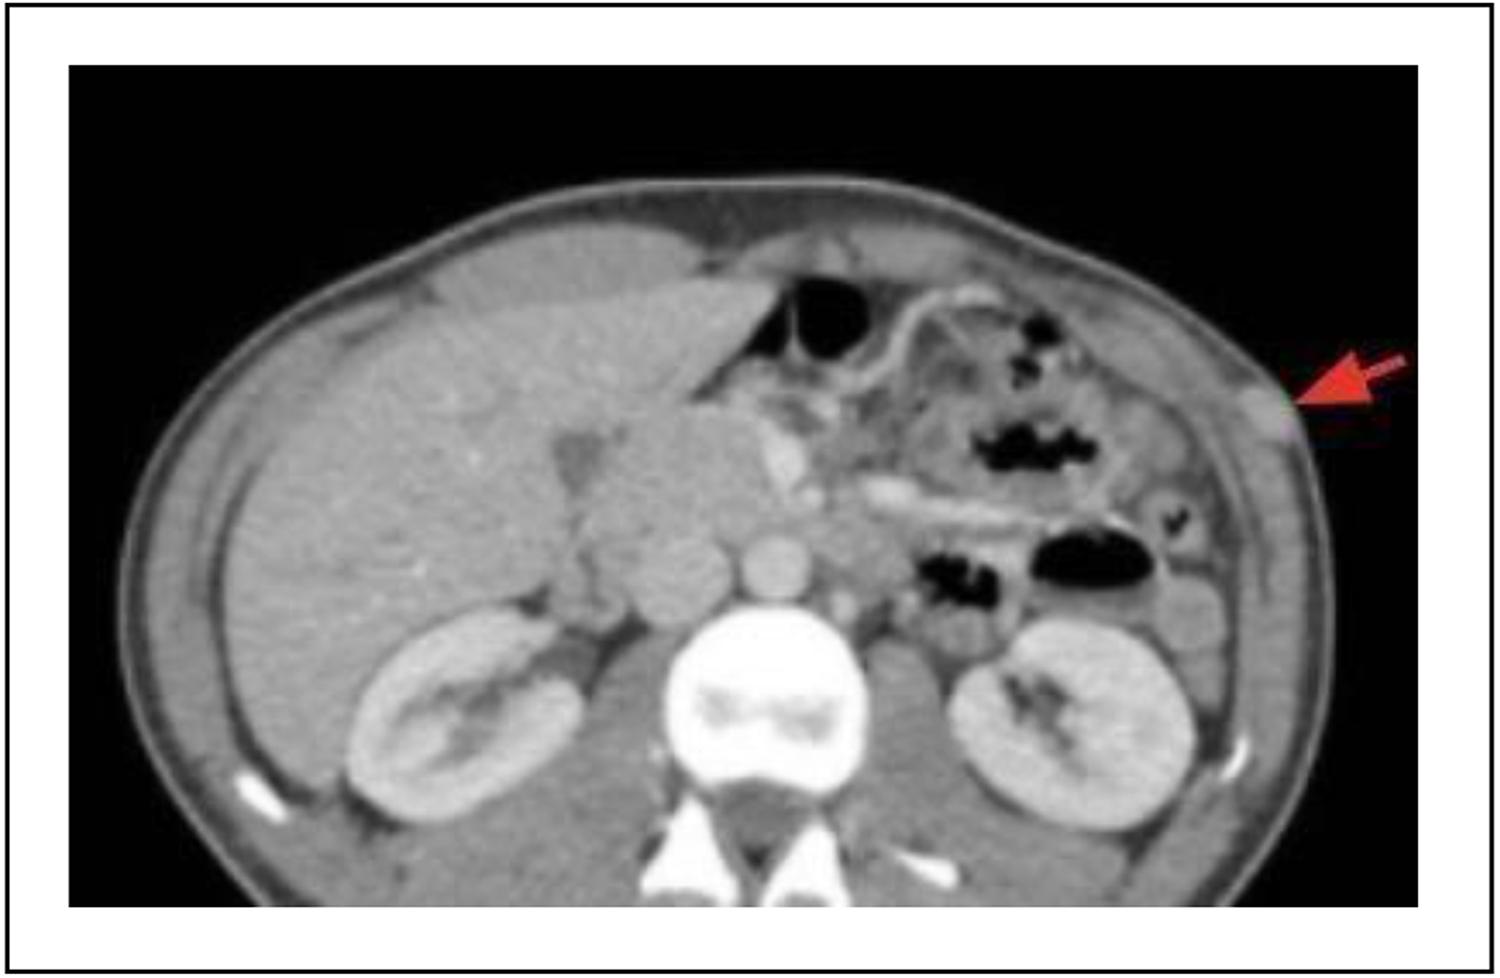

Se completó la valoración con una tomografía axial computarizada de abdomen que confirmó el diagnóstico (Figura 3).

Figura 3. Tomografía axial computada, esplenosis parietal (flecha roja).